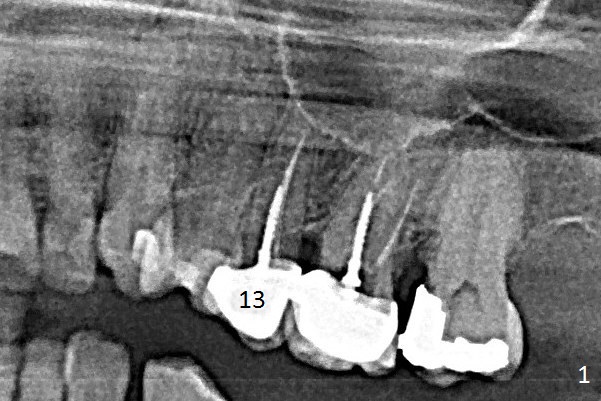

A 60-year-old woman returns to office with chief complaint "upper left crown is loose again". Clinical exam confirms #13 crown fracture at the gingival level (Fig.1,2 *). Since the native bone is short, an implant (Fig.3 green) should penetrate the sinus floor for primary stability. To protect the sinus membrane, PRF membranes (purple curved line) will be inserted prior to bone graft (red circles) and the implant. A pair abutment is expected to be 5x5 (5.7 exactly, blue) (Fig.3, pink) mm. The implant should be placed palatally to avoid buccal metal show through.